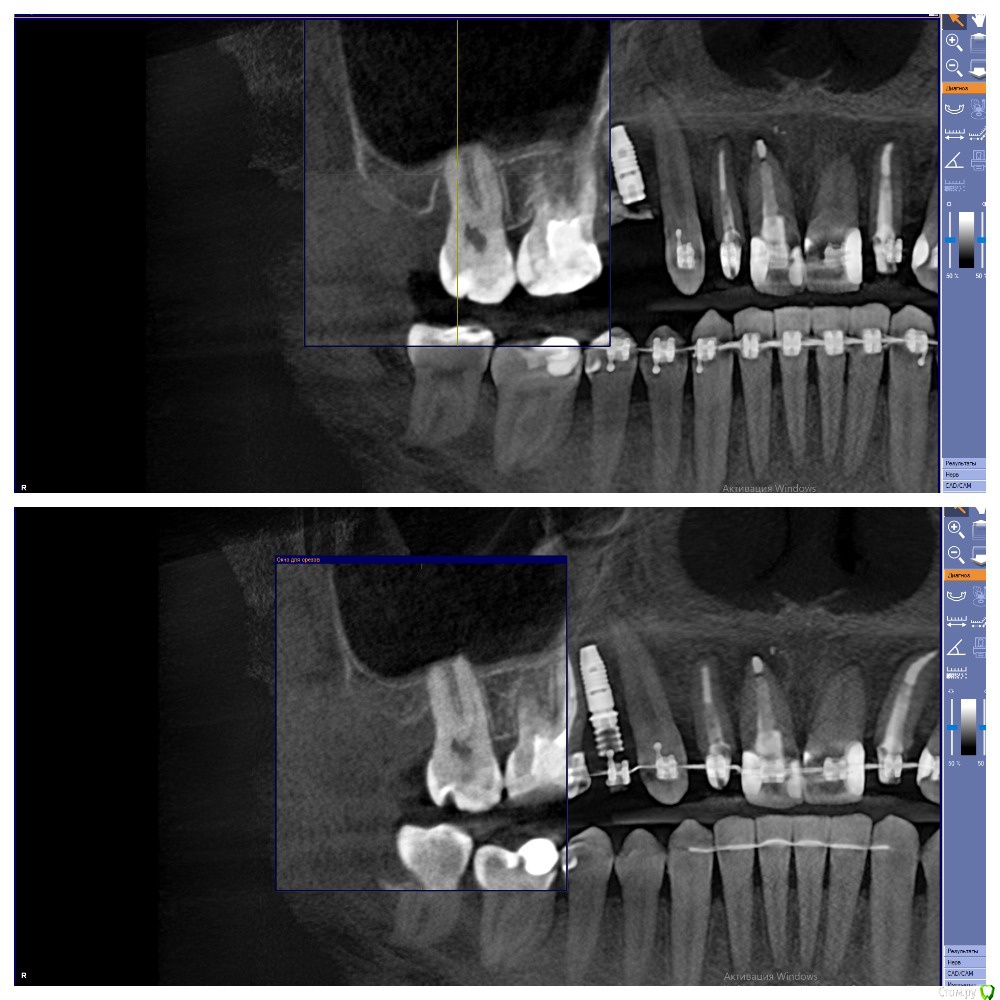

Al..ks Опубликовано 28 мая, 2020 Поделиться Опубликовано 28 мая, 2020 (изменено) Добрый день. Нужен совет. В августе 2019 года, во время установки формирователя десны чистили десневой карман у 17 (грануляции и тд) и подсыпали туда материал какой то, чтоб кость нарастить. А через пол года был план - осмотр и возможно еще подсыпать.К сожалению врач, которая это делала ушла из клиники и на консультацию через полгода пошел уже к другому.Он сделал КТ (зондом не смотрел карман) и сказал , что ничего не надо больше подсыпать, только наблюдать. Меня немного морочит - зуб немного шатается, и полость полностью не заросла костью.Вот фото КТ (сверху было, снизу стало) Изменено 28 мая, 2020 пользователем Al..ks Ссылка на комментарий

Al..ks Опубликовано 5 июня, 2020 Автор Поделиться Опубликовано 5 июня, 2020 Если вы и сами во всем разбираетесь, то зачем спрашиваете совета?, если бы у вас зуб был без перегрузки, то он бы не шатался.По этому снимку вся же предистория не видна (до брекетов - где не понятно как были контакты было: - 16 резорцинформалиновый сильно наклонен, 17, 18. Между ними иногда кровило при чистке ирригатором. 18 заболел перед самой установкой - удалили и в процессе выяснилось - нет костной стенки между ними и когда все зашили и зажило,то остался карман глубиной где-то 11мм. Ну а дальше .... Сейчас (когда его "отключили" от дуги) он шатается уже не так сильно, но по ощущениям чуть сильнее чем "подключенные" к дуге брекетов. Ссылка на комментарий